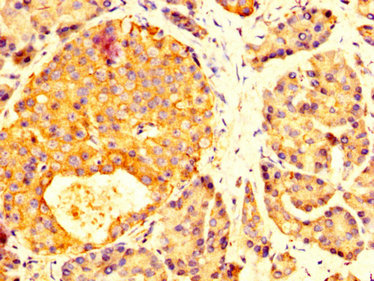

IHC image of CSB-PA859950LA01HU diluted at 1:200 and staining in paraffin-embedded human pancreatic tissue performed on a Leica BondTM system. After dewaxing and hydration, antigen retrieval was mediated by high pressure in a citrate buffer (pH 6.0). Section was blocked with 10% normal goat serum 30min at RT. Then primary antibody (1% BSA) was incubated at 4°C overnight. The primary is detected by a biotinylated secondary antibody and visualized using an HRP conjugated SP system.